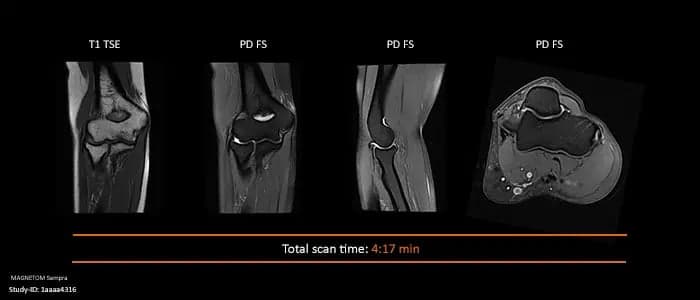

One of the few applications of AI in medicine I’ve recently used which is quite exciting is Siemens deep resolve MRI acquisition AI, which can reduce MRI scan time by > 50%